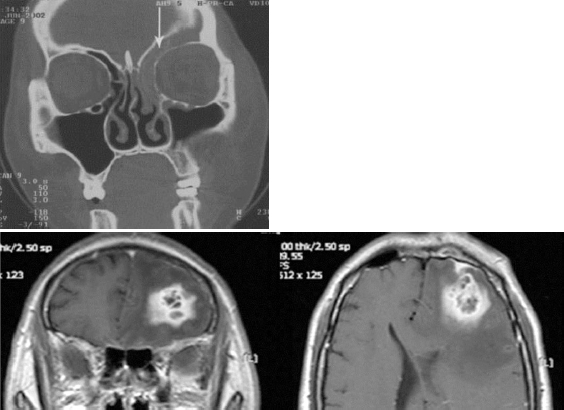

40세 남자 환자가 내원 2일 전부터 시작된 심한 두통, 지속적인 발열, 오심, 구토를 주소로 내원하여 시행한 부비동 컴퓨터단층촬영과 자기공명영상 소견이다. 이 질환에 대한 설명은 올바른 것은?

③ 안과, 신경과, 신경외과, 감염 내과 전문의 등과 함께 치료하는 것이 바람직하며 혈액뇌장벽을 통과할 수 있는 3세대 cephalosporin과 metronidazole을 병합하여 투여하는 것이 적절하다.

⑤ 일반적으로는 사골동이 두개내 합병증을 일으키는 가장 흔한 부비동이며 다음으로 전두동, 접형동, 상악동 순이다.